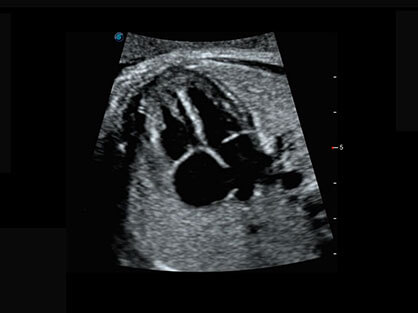

可同时显示组织结构表面和内部的轮廓信息,达到透视效果,为临床提供更丰富的诊断信息。